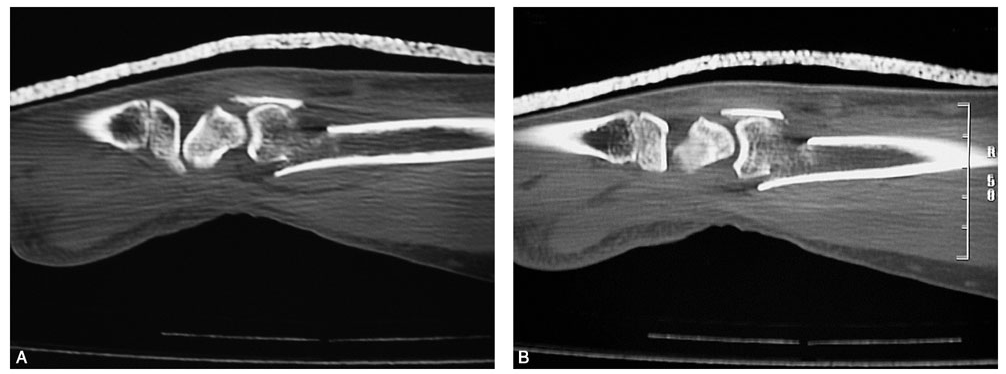

术前拍腕关节正、侧位X线片,腕关节冠状位、矢状位和水平位CT(图2-2)此患者骨缺损和无法闭合复位的骨片均在背侧,宜采用背侧入路,复位,植骨,固定。取患肢前臂远端桡背侧纵切口(图2-3)从伸拇长肌腱和桡侧伸腕长、短肌之间进入,注意保护血管神经和肌腱,显露清理折端骨缺损区域和背侧移位的骨片(图2-4复位,植骨,外固定架超关节固定(图2-5、图2-6)。术中透视骨折复位固定满意(图2-7),术后拍X线片证实(图2-8)。此手术的优点在于避免了局部存在内固定物的刺激,避免二期切开取出固定物所致的再次损伤。

图2-2 骨缺损和无法闭合复位的骨片均在背侧